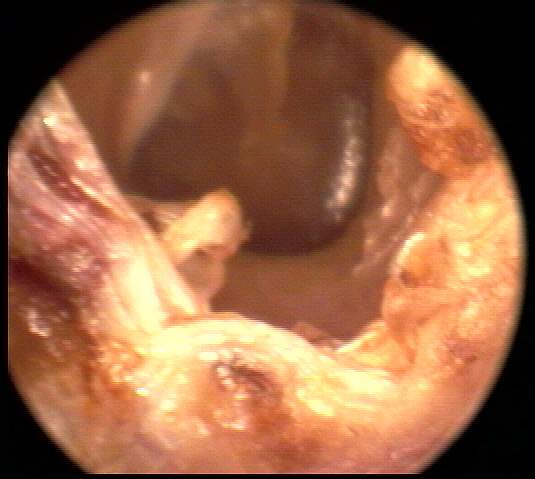

+2: Non-occlusive moderate amount present; likely to interfere with probe tube and ear-insert transducer measurements, hearing aid use, to dimensionally distort or inhibit impression-taking with the possibility of subsequent impaction. Tympanic membrane view may be partially obscured. Removal advised. EXAMPLES:+2/A(25k) | +2/B(23k) | +2/C(21k) | +2/D(21k)